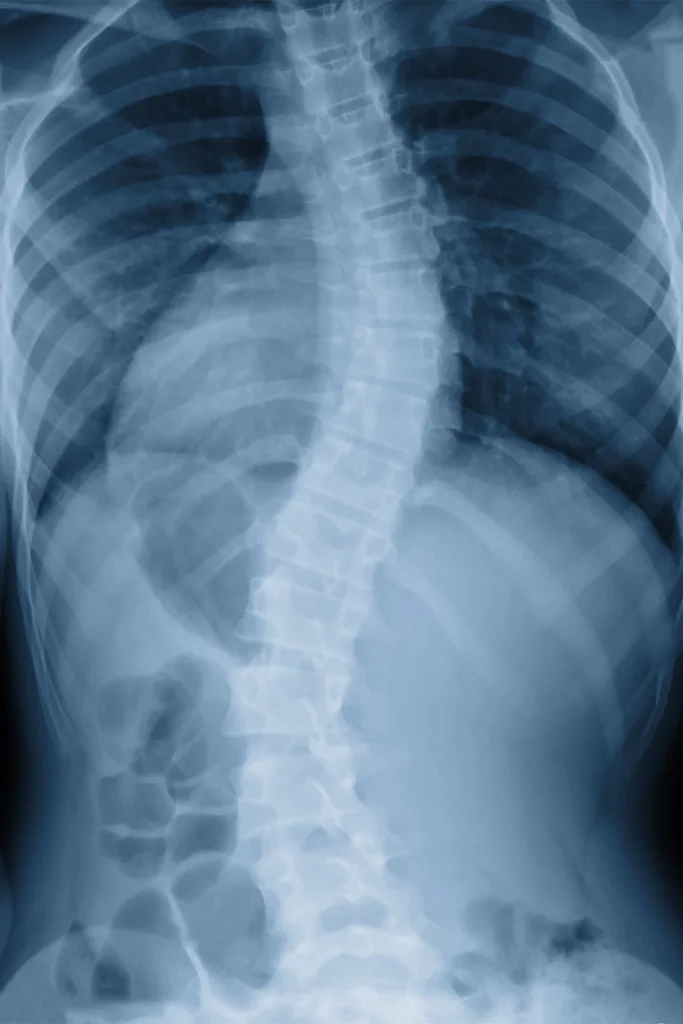

We begin with a thorough evaluation of your spine, pelvis, and lower body mechanics. Digital X-rays may be taken to rule out disc involvement or structural problems. Treatment may include chiropractic adjustments, spinal decompression therapy, and soft tissue techniques to reduce inflammation, improve alignment, and relieve nerve irritation.